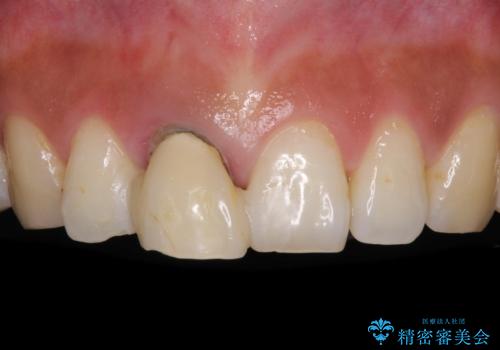

折れているのに応急処置でごまかしてきた前歯 オールセラミックブリッジによる補綴治療

- 歯根が破折しているにもかかわらず、抜歯を避けてきたため痛みが発現したとのことで来院された患者様です。

歯根破折した歯は抜歯適用となるため、速やかに抜歯を行い、傷が治り次第オールセラミックブリッジにて補綴治療を行うこととしました。